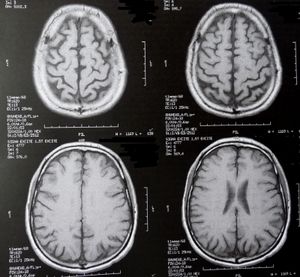

Gehirnscans: machen Verhaltensstörungen sichtbar (Foto: pixelio.de, D. Schütz) |

London (pte016/23.10.2012/11:15) Die Gehirne von Mädchen im Teenageralter, die unter Verhaltensstörungen leiden, unterscheiden sich von denen ihrer Altersgenossen. Eine im Journal of Child Psychology and Psychiatry veröffentlichte Studie hat ergeben, dass die 40 teilnehmenden Mädchen Veränderungen in den Gehirnbereichen aufwiesen, die mit Empathie und Gefühlen in Zusammenhang stehen.

Bei der aktuellen vom Wellcome Trust http://wellcome.ac.uk und dem Medical Research Council http://www.mrc.ac.uk finanzierten Studie führten die Forscher bei 22 Mädchen mit Verhaltensstörungen Gehirnscans durch und verglichen diese mit 22 nicht verhaltensauffälligen Mädchen. Es zeigte sich, dass bei verhaltensauffälligen Teenagern beiden Geschlechts die Amygdala kleiner war.

Sie ist dafür verantwortlich zu erkennen, ob sich andere Menschen fürchten und spielt auch eine Rolle dabei selbst Angst zu empfinden. Mädchen mit Verhaltensstörungen verfügten auch über weniger graue Gehirnsubstanz in der Isula, jenem Bereich des Gehirns, der mit Gefühlen und dem Verstehen der eigenen Emotionen in Zusammenhang gebracht wird.

Bei verhaltensgestörten Jungen war dieser Bereich jedoch größer als bei ihren gesunden Altersgenossen. Die möglichen Ursachen dafür sind derzeit noch nicht erforscht. Die Gehirne derer, die über die schwersten Verhaltensstörungen verfügten, unterschieden sich auch am meisten von denen mit normalen Verhaltensmustern.